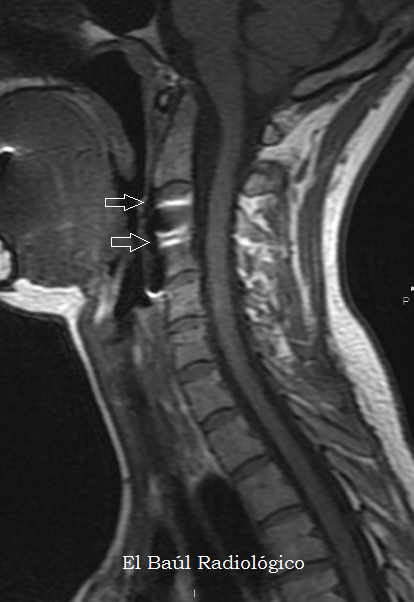

FIGURA 4) Secuencia FSE-T1. La placa metálica de titanio produce artefactos de susceptibilidad magnética (flechas) que impiden la correcta visualización de los cuerpos vertebrales en los que está insertada, pero no dificultan la exploración de la médula y el canal espinal.

(FSE-T1 MRI Sequence. The titanium metal plate produces magnetic susceptibility artifacts (arrows) that prevent the correct visualization of the vertebral bodies in which it is inserted, but does not difficult the exploration of the cord and the spinal canal).